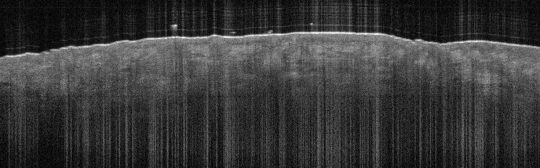

VA40: Right Upper Arm, Adjacent, Normal